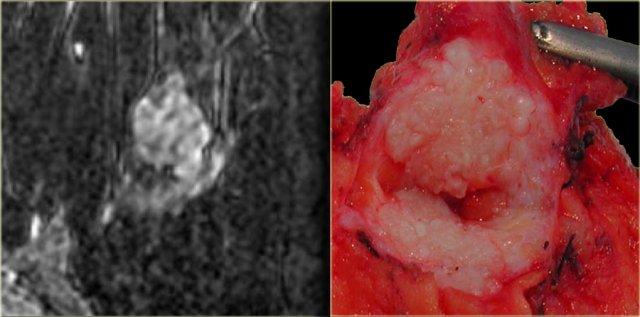

Hình ảnh ngoài cùng bên trái cho thấy một khối có bờ tua gai, tức là khả năng ác tính 80%.

Bên cạnh đó là mẫu bệnh phẩm đại thể tương ứng.

Có thể thấy các tua gai xâm lấn vào mô xung quanh trong cả hai hình.

Tương tự như trên nhũ ảnh, tổn thương này có khả năng ác tính cao và sẽ được phân loại BIRADS 5.